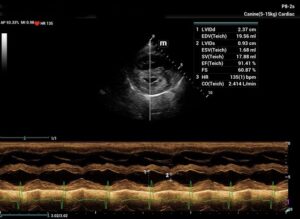

Chronic stage C MVD.TID Pimo and Lasix(high dose), ACEi and Spirono. Doing well. Recheck: Idexx GHP= CBC-NSF ,SDMA 15,BUN 14.1mmol/L, Creat 79umol/L. US: Cornell Indx LVd=1.46(prev2.1), LV septal flattening with diastolic dip,LAAO=2.47,Evel1.45m/s, TVregPG-68mmHg,HV distension-mod ascites.LV and LA underloading via diuretics and PHT (mild PHT past).PHT more pre vs post cap based on small LVsize? Consider Sildenafil/L Arg.Concerned about developing L CHF.Is CHF less likely adding PDE5i with MVD/PHT in underloaded LV than same scenario with vol overloaded LV at similar staging. MVPG=120.3mmHg

Thanks. Not sure if any sig. MV stenosis?? My experience limited.3 PWD from diff times. Ls7 vid. is from 2024,initially thinking reverse remodelling where the lasix lowering preload and Pimo is decreasing LV size via decreased resist/increase cxn while LA no change because it’s a chronic filled remodeled saggy bag receiving Regurge volume??